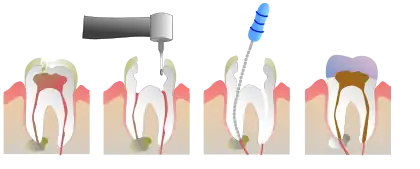

In the oral cavity 100% of people diagnosed with TDO have taurodontism which is characterized by vertically enlarged pulp chambers at the expense of the roots of the teeth; the floor of the pulp chamber and furcation is moved apically down.[1] This is due to the failure of the Hertwig epithelial root sheath which maps the shape of the forming tooth roots during active differentiation. Amelogenesis imperfecta, an abnormal formation of the enamel or external layer of the crown of the tooth, may also be present where the tooth enamel may be thin or absent. There are several clinical subsets of amelogenesis imperfecta, but common to TDO is the hypoplastic-hypomaturation subtype;[3] the hypomaturation-hypoplastic is less common in individuals with TDO. The difference between the 2 dominant subtypes is the changes seen in the enamel matrix, and the phenotypic type that predominates. The hypoplastic-hypomaturation type of amelogenesis imperfecta with TDO occurs where the tooth enamel depicts a generalized pitted pattern, with open contacts between the teeth as well as an open bite. A smaller number of cases are of the hypomaturation-hypoplastic case type, in which the enamel structure is softer due to the under maturation of ameloblasts during development. Mandibular prognathism also called a severe underbite, is also a prominent feature in TDO. Prognathism defects are diagnosed based the level of severity that this condition interferes with being able to chew or speak properly.

Due to improper tooth development, TDO patients suffer from high rates of dental caries causing dental abscess. The under maturation of the enamel causes the tooth structure to be softer, and more susceptible to the effects of bruxism due to abnormalities in skeletal development. The oral abnormalities are evaluated by radiographs and visual examination. Oral radiographs are frequently repeated due to the high incidence of infection due to abnormal biting patterns seen in TDO cases.

Endodontic procedures are routinely recommended due to treatdental pulp exposure or periodontal abscess. Maxillofacial surgery may be required to establish a more appropriate mastication, skeletal, and esthetic relationship vertically between the teeth to improve functioning. Esthetic procedures such as dental crown (dentistry) or veneer (dentistry) are often performed to improve the physical look of the teeth and to strengthen the weak enamel caused by TDO.[1]